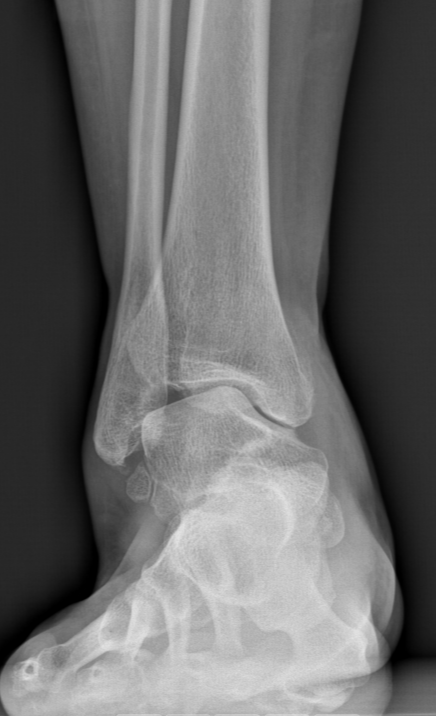

术前踝关节侧位X线

术后侧位X线

武勇主任团队给他做了3D打印导板辅助下人工全踝关节置换术。

这种手术适合踝关节病严重的患者,通过替换病变的关节结构,能帮着缓解疼痛、恢复关节活动,让老人日常走路更自在些。